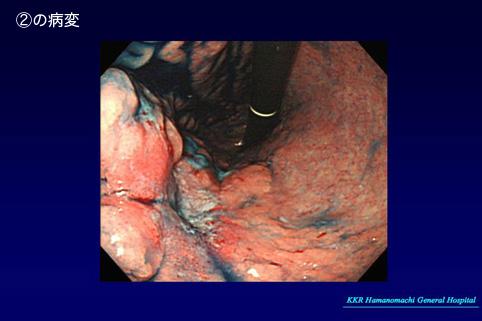

질환(병리주체)의 분류 악성 상피성종양/기타

부위(장기별) 위(부위)/체부

검사방법 내시경

종양의 육안분류 3형(궤양침윤형)/

종양의 최대경(밀리미터) 25~29

종양의 심달도 mp

다발종양(동일 장기) 유(동시성)